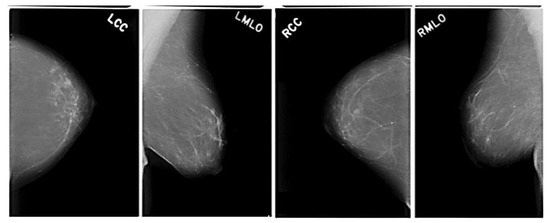

Basically, there are two broad categories of breast cancer: benign and aggressive. There were 277,524 50 × 50 patches made (78,786 IDC-positive and 78,738 IDC-negative). Each patch has the filename uxXyYclassC.png, for example, 10253idx5x1351y1101class0.png. X, Y, and u stand for the patient ID. No-10253idx5, and x and y stand for the coordinates; 1 indicates IDC, and 0 is non-IDC. An example of a histopathological image of a breast is shown in the following diagram in Figure 6.

Figure 6.

Sample breast cancer image dataset.

We have utilized 7026 images from the dataset to teach the framework, and another 2342 for evaluation. The performance parameters of the model are evaluated and depicted in the following formulae. The LCC (Left Craniocaudal), LMLO (Left Mediolateral Oblique), RCC (Right Craniocaudal) and RMLO (Right Mediolateral Oblique) are clearly shown in above Figure 6.